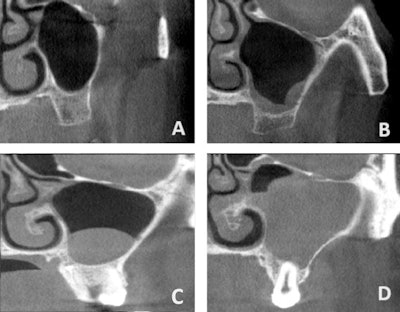

Maxillary sinus conditions identified via CBCT. (A) Clear sinus, (B) mucosal thickening, (C) cyst/polyp, (D) opacification (≥ 50% of sinus volume). Images and captions courtesy of Küçükkurt. Licensed under CC BY-NC-ND 4.0.

Sinus pathologies were found in 39.5% of sinuses and affected 54.8% of patients. Mucosal thickening was the most common condition (61%) followed by cysts or polyps (27.6%) and opacifications (11.4%). Men had a significantly higher rate of cysts and polyps (p = 0.020), while mucosal thickening did not vary by gender, Küçükkurt wrote.

Furthermore, odontogenic factors were present in 65.2% of affected sinuses, especially in mucosal thickening cases, with periapical lesions, both untreated and treated with RCT, strongly linked to pathology (p < 0.0001 and p = 0.013), unlike RCT teeth without lesions (p = 0.411). Complete sinus opacification occurred in 5% of cases, and patients ages 41 to 60 had a significantly higher rate of bilateral sinus involvement (p < 0.0001). Mucosal thickening was more often bilateral, while cysts were typically unilateral (p = 0.003).